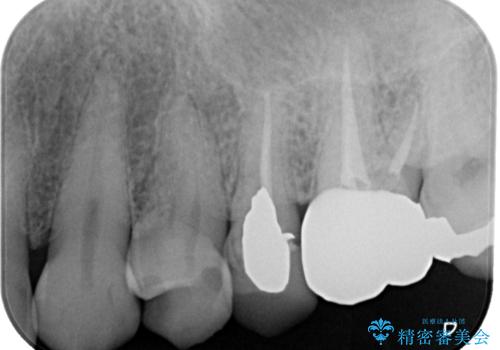

- 銀歯が取れたとのことで来院された患者様です。患者様の歯をあまり削りたくないというご希望に添い、セラミックインレーにて治療を行うこととなりました。

拡大鏡視野下で、保険のプラスチック、虫歯の除去を行い、セラミックインレーに適した形に整えました。

歯と歯茎の間に圧排糸と言われる糸を入れてシリコーン印象材にて精密な型どりをしました。

セラミックインレーの装着時には、唾液の侵入を防ぐために、ラバーダム防湿を行いました。